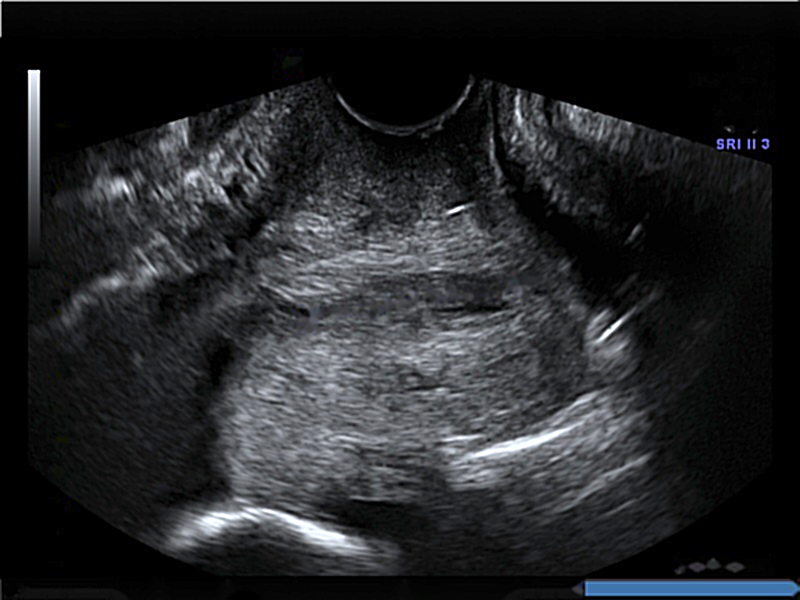

Dataset: The original dataset consists of 354 two-dimensional transvaginal cervical ultrasound images. Data were collected from female volunteers during check-ups conducted in the first and second trimesters of pregnancy. Data includes 319 images of the pregnancy control group and 35 images of premature deliveries which reflects the statistical occurrence of this phenomenon in reality. Note that to get information about image labels, we waited for the pregnancy result of each patient. The data was provided by two different clinics: King’s College London and Medical University of Warsaw. All images have been annotated by several independent gynecologist experts via our own annotation tool. Sample images from the data set are depicted in Fig. 1.

The annotations received contained the study identifier and four control points which allowed for the drawing of cubic Bézier curves that outlined the shape and position of the cervix in the image. Bézier curves were used to create masks for cervical segmentation.

Preprocessing: We first removed the manually embedded annotations in the form of yellow and green crosses placed by gynecologists during routine ultrasound examinations. For this purpose, we used the inpainting algorithm proposed by Telea [8], which was used in a similar case by [9]. This allowed our algorithm to learn from the images rather than learning manually embedded annotations. Note, these annotations were unrelated to the task we were doing. In order to improve model generalization we divided the dataset into three parts: training, test, and validation. Then we did a 50:50 data augmentation between the preterm class and control on each subset to avoid heavily focusing on the majority class by classification algorithm. We applied various types of data augmentation techniques such as cropping, random rotation in the range of -15 to +15 degrees and adding contrast, brightness or noise. As a result the set was expand to 6354 images. On the dataset, based on created annotations for each examination by several gynecological experts, we created segmentation masks, which were used to train the neural network in the segmentation task.